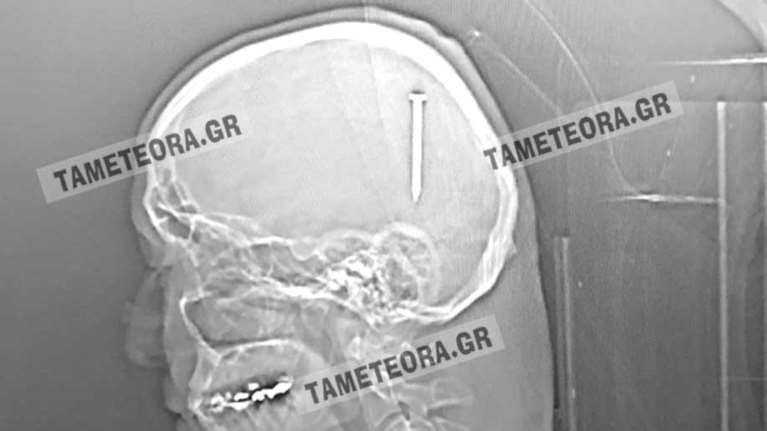

ΔΕΝ ΕΝΙΩΘΕ ΠΟΝΟ 19 Απρ 2022 | 08:14

Απίστευτο: Καρφί 5 εκατοστών σφηνώθηκε στο κεφάλι άνδρα στην Καλαμπάκα [εικόνες]

Από θαύμα ζει ένας ένας κάτοικος της Καλαμπάκας, καθώς βρέθηκε ξαφνικά με ένα καρφί 5 εκατοστών σφηνωμένο στο κεφάλι του.